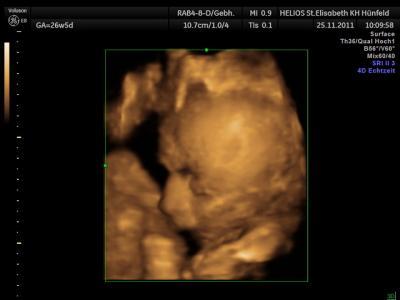

Bild zu Wunsch KS - wie läuft das ab und macht das jemand von Euch - Forum für Februar - Mamis